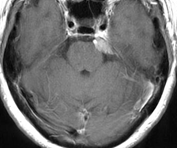

傍矢状静脈洞髄膜腫

上矢状静脈とは、頭の中央を走行する太い静脈です。その静脈の壁に接した硬膜から発生する髄膜腫は、無症状のこともありますが、腫瘍のサイズが大きいと手足の運動を司る場所(中心前回と言います)が圧迫を受けるために麻痺やけいれんを生じることがあります。

(術前MRI)

(術後MRI)

ところが、たとえ腫瘍が小さくても、下の画像に示すように、造影される病変(左)に比べ、脳浮腫(右;白く広がっている部分)が広い範囲に拡大していると、腫瘍の大きさが小さいにも関わらず症状(この場合右足の麻痺やてんかん発作)が重症化することが多いです。腫瘍摘出を行なうと、術後3~4週間で浮腫は消失します。